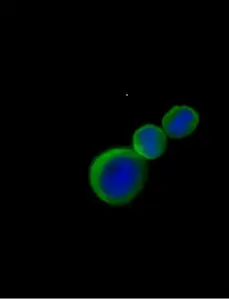

Example images from patient blood samples

Cluster of epithelial CTCs - breast